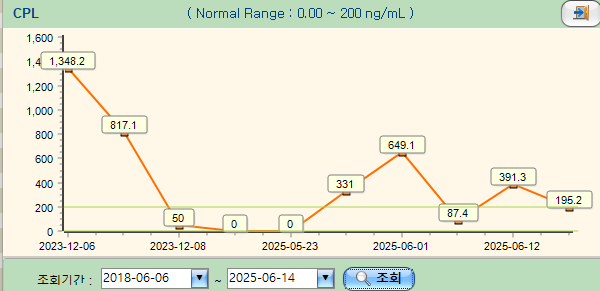

해당 환자는 과거부터 반복적인 췌장염 병력이 있었던 환자로, 내원 당시 혈액검사에서는 현저한 백혈구 증가와 함께 CRP 상승, 그리고 cPL 증가가 확인되어 전신적인 염증 반응과 췌장 활성화 상태가 동반된 것으로 판단되었습니다.

다음은 치료 결과에 따른 혈액검사 추이입니다.

간수치 모두, cPL(췌장염) 수치와 함께 같이 움직이는 것을 볼 수 있으며, 차차 개선세로 수렴하고 있는 모습입니다.